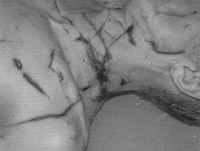

During homosexual intercourse, a 52-year-old man (the eventual victim) demanded further bizarre sexual activities from his partner, who refused. Thereupon, the man tried to hit his partner's head with a beer bottle. The partner escaped this assault and subsequently repeatedly hit the victim's head with a beer bottle. The bottle burst into pieces but the victim did not lose consciousness. During the fight that followed, the victim sustained several stab wounds. At autopsy, exsanguination caused by several stab wounds and incised wounds of the thorax and the neck (Fig on the right) was determined as cause of death. The incised wounds were attributable to assaults with a knife derived from glass splinters, too. In addition to the incised wounds that were caused by the glass splinters, lacerations of the scalp that were attributed to the blow with the beer bottle were observed. These injuries comprised large-sized hematomas with several short and angled lacerations, as well as streaky impressions of the tabula externa accompanied by subarachnoidal hemorrhage.